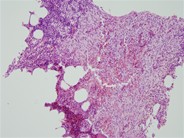

Mast cells stain positive (brown) for CD117 (c-kit). C-kit D816V mutation was detected in the bone marrow. (400×)